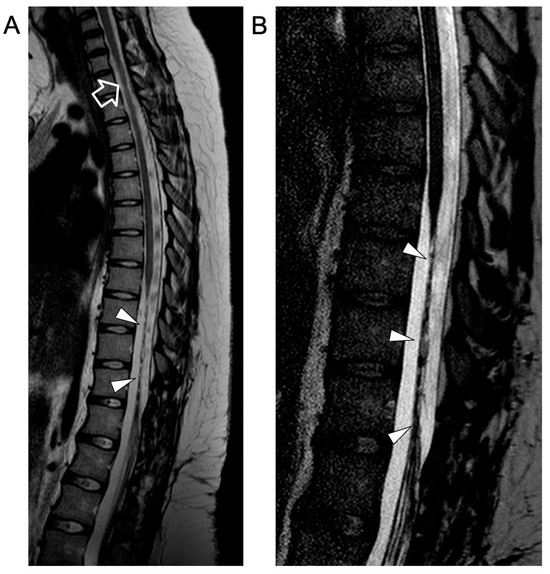

In the following months, repeated MRI studies revealed progressive disappearance of the intradural extramedullary lesions, regression of cauda equina contrast enhancement, and chronic evolution of the spinal cord lesions. At the last follow-up, performed at 18 years of age, the neurological examination was unchanged, showing complete paralysis of the lower limbs. Spinal MRI revealed stable atrophy and gliotic changes of the affected dorsal spinal cord and conus medullaris (Figure 4).

Figure 4.

Contrast-enhanced spinal MRI performed at the last follow-up, several months after clinical onset. Sagittal T2-weighted (A) and 3D driven equilibrium (DRIVE) (B) images reveal a focal area of mild spinal cord thinning at the superior dorsal level (empty arrow) and an extended segment of severe spinal cord atrophy in the inferior dorsal spinal level (arrowheads).